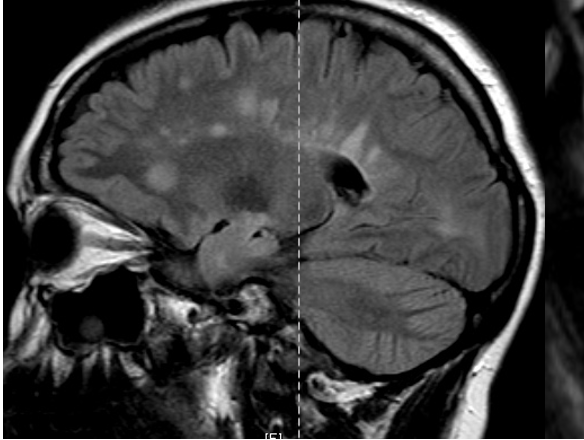

In the image below is a patients with multiple sclerosis sagittal scan from the brain. What are the white area in this image a sign of?

1 - myelinated areas

2 - neuronal cell bodies

3 - unmyelinated areas

4 - glial scars called sclerela

A